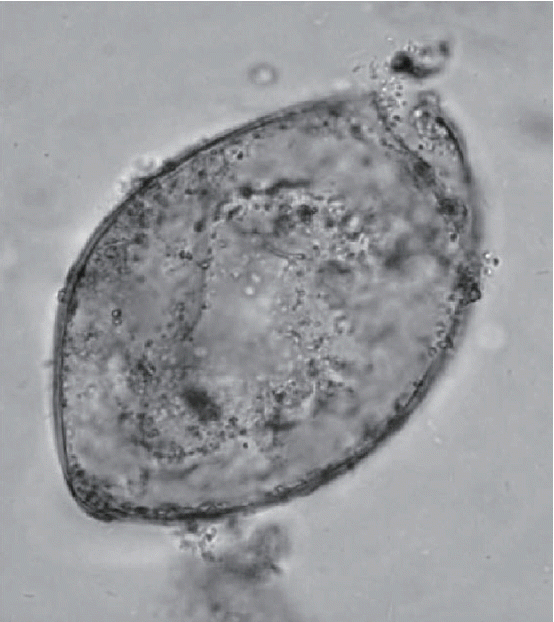

Another ground-breaking aspect of the Peruaçu study was the molecular refinement of microscopic diagnosis of trematode eggs (Fig. 3). Coprolites were present in the mummy and were analyzed by Sianto and her colleagues [19]. Eggs of a common intestinal parasite, hookworm, and an unusual intestinal parasite, Echinostoma spp. were found. Hookworm eggs were relatively rare in this sample, and only 5 were observed. Echinostoma spp. eggs were abundant and numbered 8,300 eggs per gram of coprolite. This suggested that the individual had a true infection. The morphology of the eggs could be described with certainty and were consistent the Echinostoma genus. The species level diagnosis could not be reached with certainty, but the eggs were most consistent with those of Echinostoma luisreyi. Leles and her colleagues [21] showed that the DNA sequence of the ancient eggs was consistent with the species Echinostoma paraensei. Therefore, molecular biology led to a more refined diagnosis at the species level.

Fig. 3

Echinostome egg as illustrated in Sianto’s original article describing the egg morphology [19].

Fig. 3 Echinostome egg as illustrated in Sianto’s original article describing the egg morphology [19].